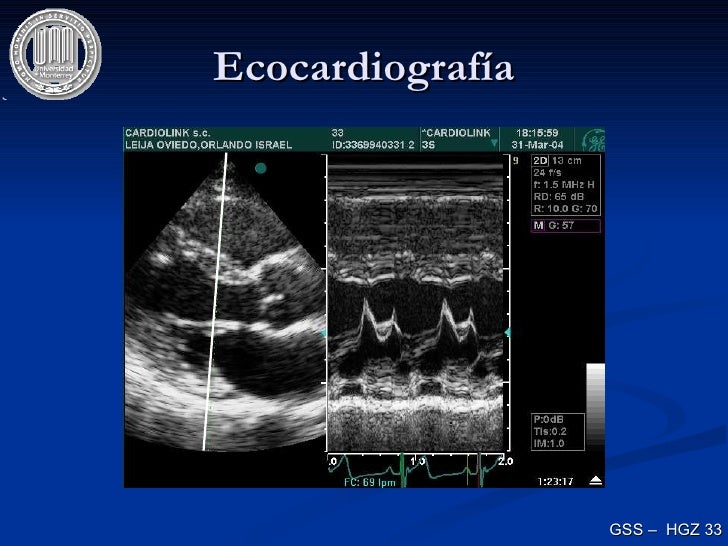

Ecocardiografía Tapse Ecocardiografia Valori Questo intervento viene eseguito quando è presente una dilatazione aneurismatica della porzione iniziale dell’aorta (radice aortica e aorta ascendente) e nei casi di dissezione dell’aorta. Mitralic annular plane excursion (normale > 10 mm). Referto ecocardiogramma ventricolo sx di normali dimensioni e spessori. La valutazione della ef e' diversa tra eco e rm e ciascuno deve essere correlato ai valori ritenuti. Tapse Ecocardiografia Valori.